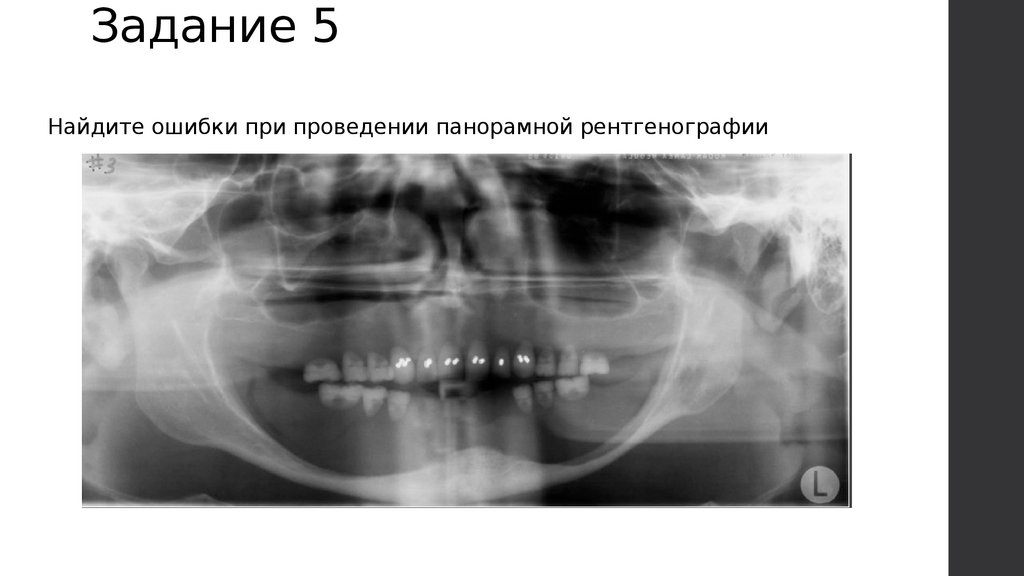

Задание 5

Найдите ошибки при проведении панорамной рентгенографии